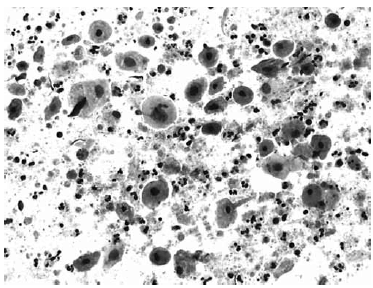

Nas questões de números 46 a 60, assinale a alternativa que melhor corresponde ao diagnóstico do quadro microscópico apresentado.